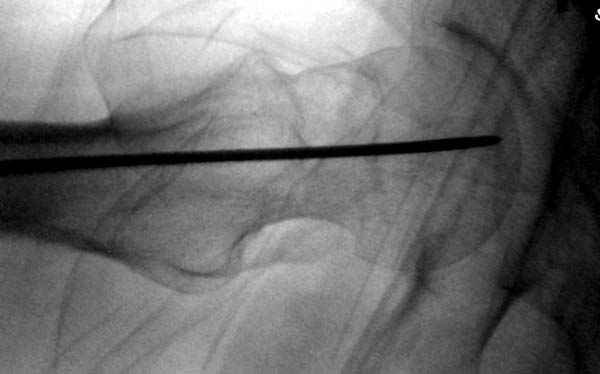

На второй день после выписки упал дома. Снимки приложены. Коллеги рекомендуют удаление шурупа и вытяжение. Что делать?

Привет из солнечного Будапешта с Eurotrauma-2008. Да, замечательный пример. Получается, профилактику расхождения отломков шейки надо было проводить каким-то реконструкционным или проксимальным гвоздем, причем сразу длинной версией. Сейчас, наверно, так и надо бы сделать.

Убрать винты, каким-то джойстиком в вертельной области сделать репозицию шейки, фиксировать ее спицами, а дальше вправлять и фиксировать как вертельный перелом.

Но ведь и головка бедра сползла в варус - отчего ограничились только фиксацией подвертельного перелома, а не убрали винты и не сделали репозицию шейки?